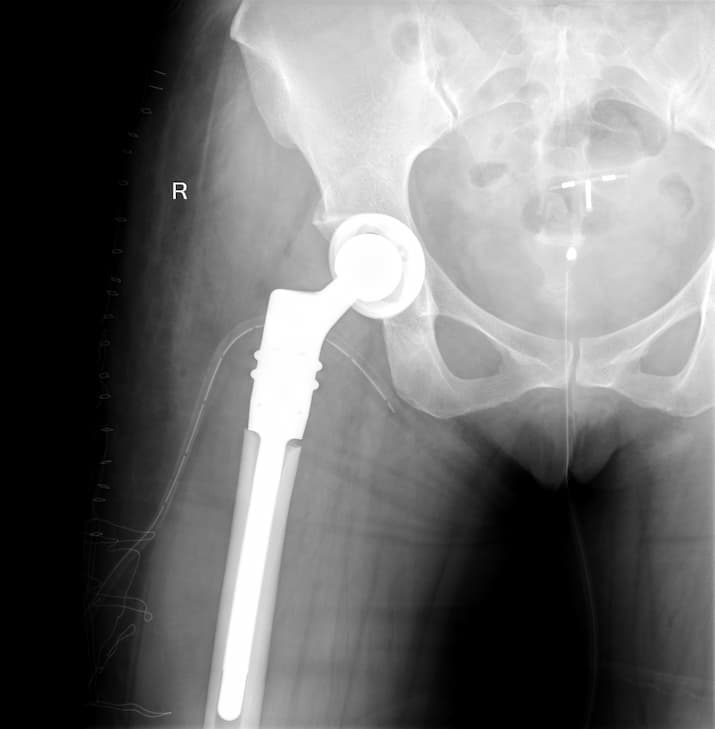

Түнхний толгой хэсгийн цусан хангамжийн алдагдалын улмаас үхжилт өөрчлөлттэй өвчтөний мэс заслын өмнөх болон дараах рентген зураг

Түнхний үе бүтэн солих мэс засал (THA) image1Түнхний үе бүтэн солих мэс засал (THA) image2